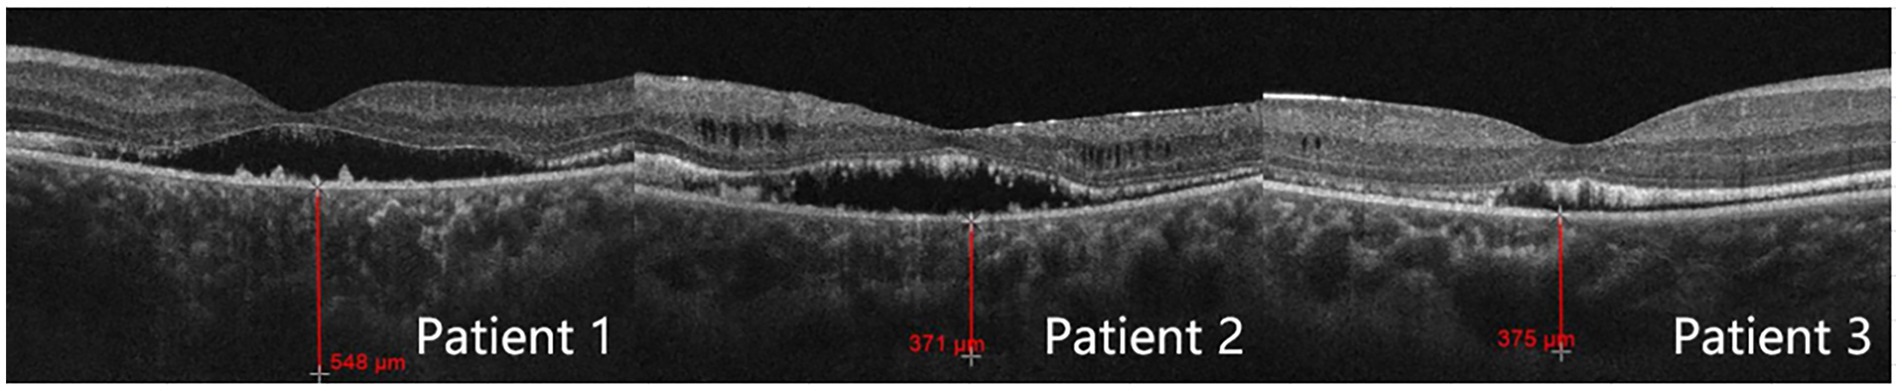

Ultrasound biomicroscopy

All three patients presented with iris bulging, anterior displacement of the ciliary body, and obstruction of the scleral spur at the iris root. The lens was in a normal position. For patients 1 and 2, one quadrant of the chamber angle was open with an extremely narrow gap, and the rest was all closed. For patient 3, complete angle closure was observed in all four quadrants, and the peripheral iridotomy incision was patent at the 1 o’clock position (Figure 2).

Figure 2

Ultrasound biomicroscope examination results. Patients 1 and 2: mild iris bulging, mild anterior displacement of the ciliary body, open temporal quadrant with an extremely narrow gap, all other quadrants closed, normal lens position. Patient 3: anterior displacement of the ciliary body in all four quadrants, scleral protrusion blocked by the iris root, chamber angle completely closed, patent peripheral iridotomy incision at the 1 o’clock position.